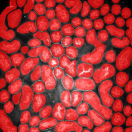

Our proposed method uses this inhomogeneity correction technique as a preprocessing step for both training and inference. Examples of original and inhomogeneity corrected images are shown in Figure 3a and Figure 3b, respectively.

The first row in Figure 3 displays an original microscopy image (), its inhomogeneity corrected version (), and manually delineated groundtruth (), respectively. For brevity we have omitted the superscript in the notation. The second row shows segmentation results of various 3D methods such as 3D region-based active contours [10] (3Dac), 3D active contours with inhomogeneity correction [11] (3DacIC), and 3D Squassh presented in [12] (3Dsquassh). Similarly, the third row portrays various segmentation methods particularly designed for tubular structure segmentation such as ellipse fitting method presented in [15] (Ellipse Fitting), the Jelly filling method in [20] (Jelly Filling), and tubule segmentation using steerable filter [21] (Steerable Filter). Finally, the last row shows segmentation results of our proposed CNN architecture without inhomogeneity correction [27] (2DCNN) and with inhomogeneity correction (2DCNNIC).

For visual comparison we highlighted groundtruth regions in red, segmented tubule regions in green, and background in black. As observed in Figure 3, our proposed method appeared to perform better than the other six methods shown in the second and third rows by distinguishing tubules and was similar performance to 2DCNN. Note that since some methods such as Ellipse Fitting, Jelly Filling, and Steerable Filter only segmented boundaries of tubule structures, tubule interiors were filled in order to perform a fair comparison using connected components with a -neighborhood systems. Also, based on the assumption that tubule regions should contain lumen, if a filled region contained lumen pixel, the region was identified as a tubule region. However, if a filled region did not contain any lumen pixels, the region was considered as a background region.